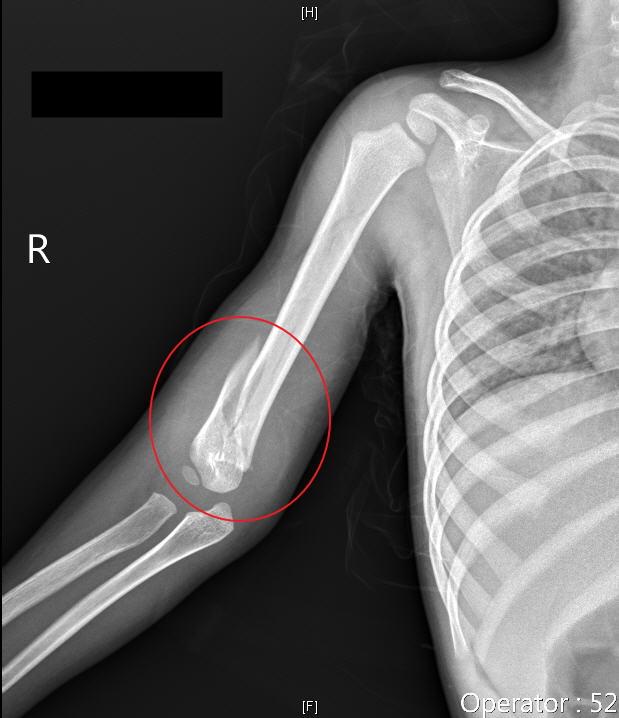

嘉義基督教醫院急診近日接獲3歲男童因右手臂腫痛帶來就醫, 醫師進行身體評估時,發現男童身上有不尋常的舊燙傷痕跡。X光顯現右手呈螺旋骨折,與家屬描述的受傷...